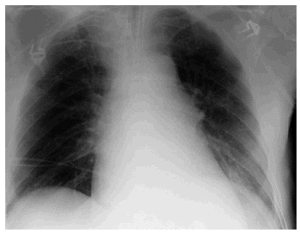

Paciente de 72 años de edad ingresado en Unidad de Cuidados Intensivos (UCI) con insuficiencia respiratoria global por una reagudización de enfermedad pulmonar obstructiva (EPOC). El paciente tiene dificultades para la desconexión de la ventilación mecánica por atelectasias de repetición y acidosis respiratoria grave. En la figura 1 se observa la radiografía de tórax en ventilación mecánica y en la figura 2 una de la imágenes de atelectasia al reducir el soporte ventilatorio. Se realizó electromiograma de diafragma mediante punción del pilar anterior por acceso retroesternal, en el que aparecieron datos de denervación (fibrilaciones y ondas rítmicas de denervación "marcadas con un circulo rojo") (fig. 3). El paciente fue dado de alta de UCI y del hospital con soporte ventilatorio parcial.

Figura 2.